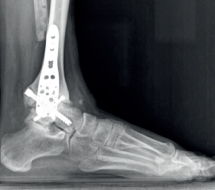

La cirugía abierta

Se trata de un tipo de cirugía convencional que permite al cirujano acceder al área afectada a través de una incisión en la piel y disección hasta llegar a la zona afectada y resolver el problema.

Image

radiografia-pie